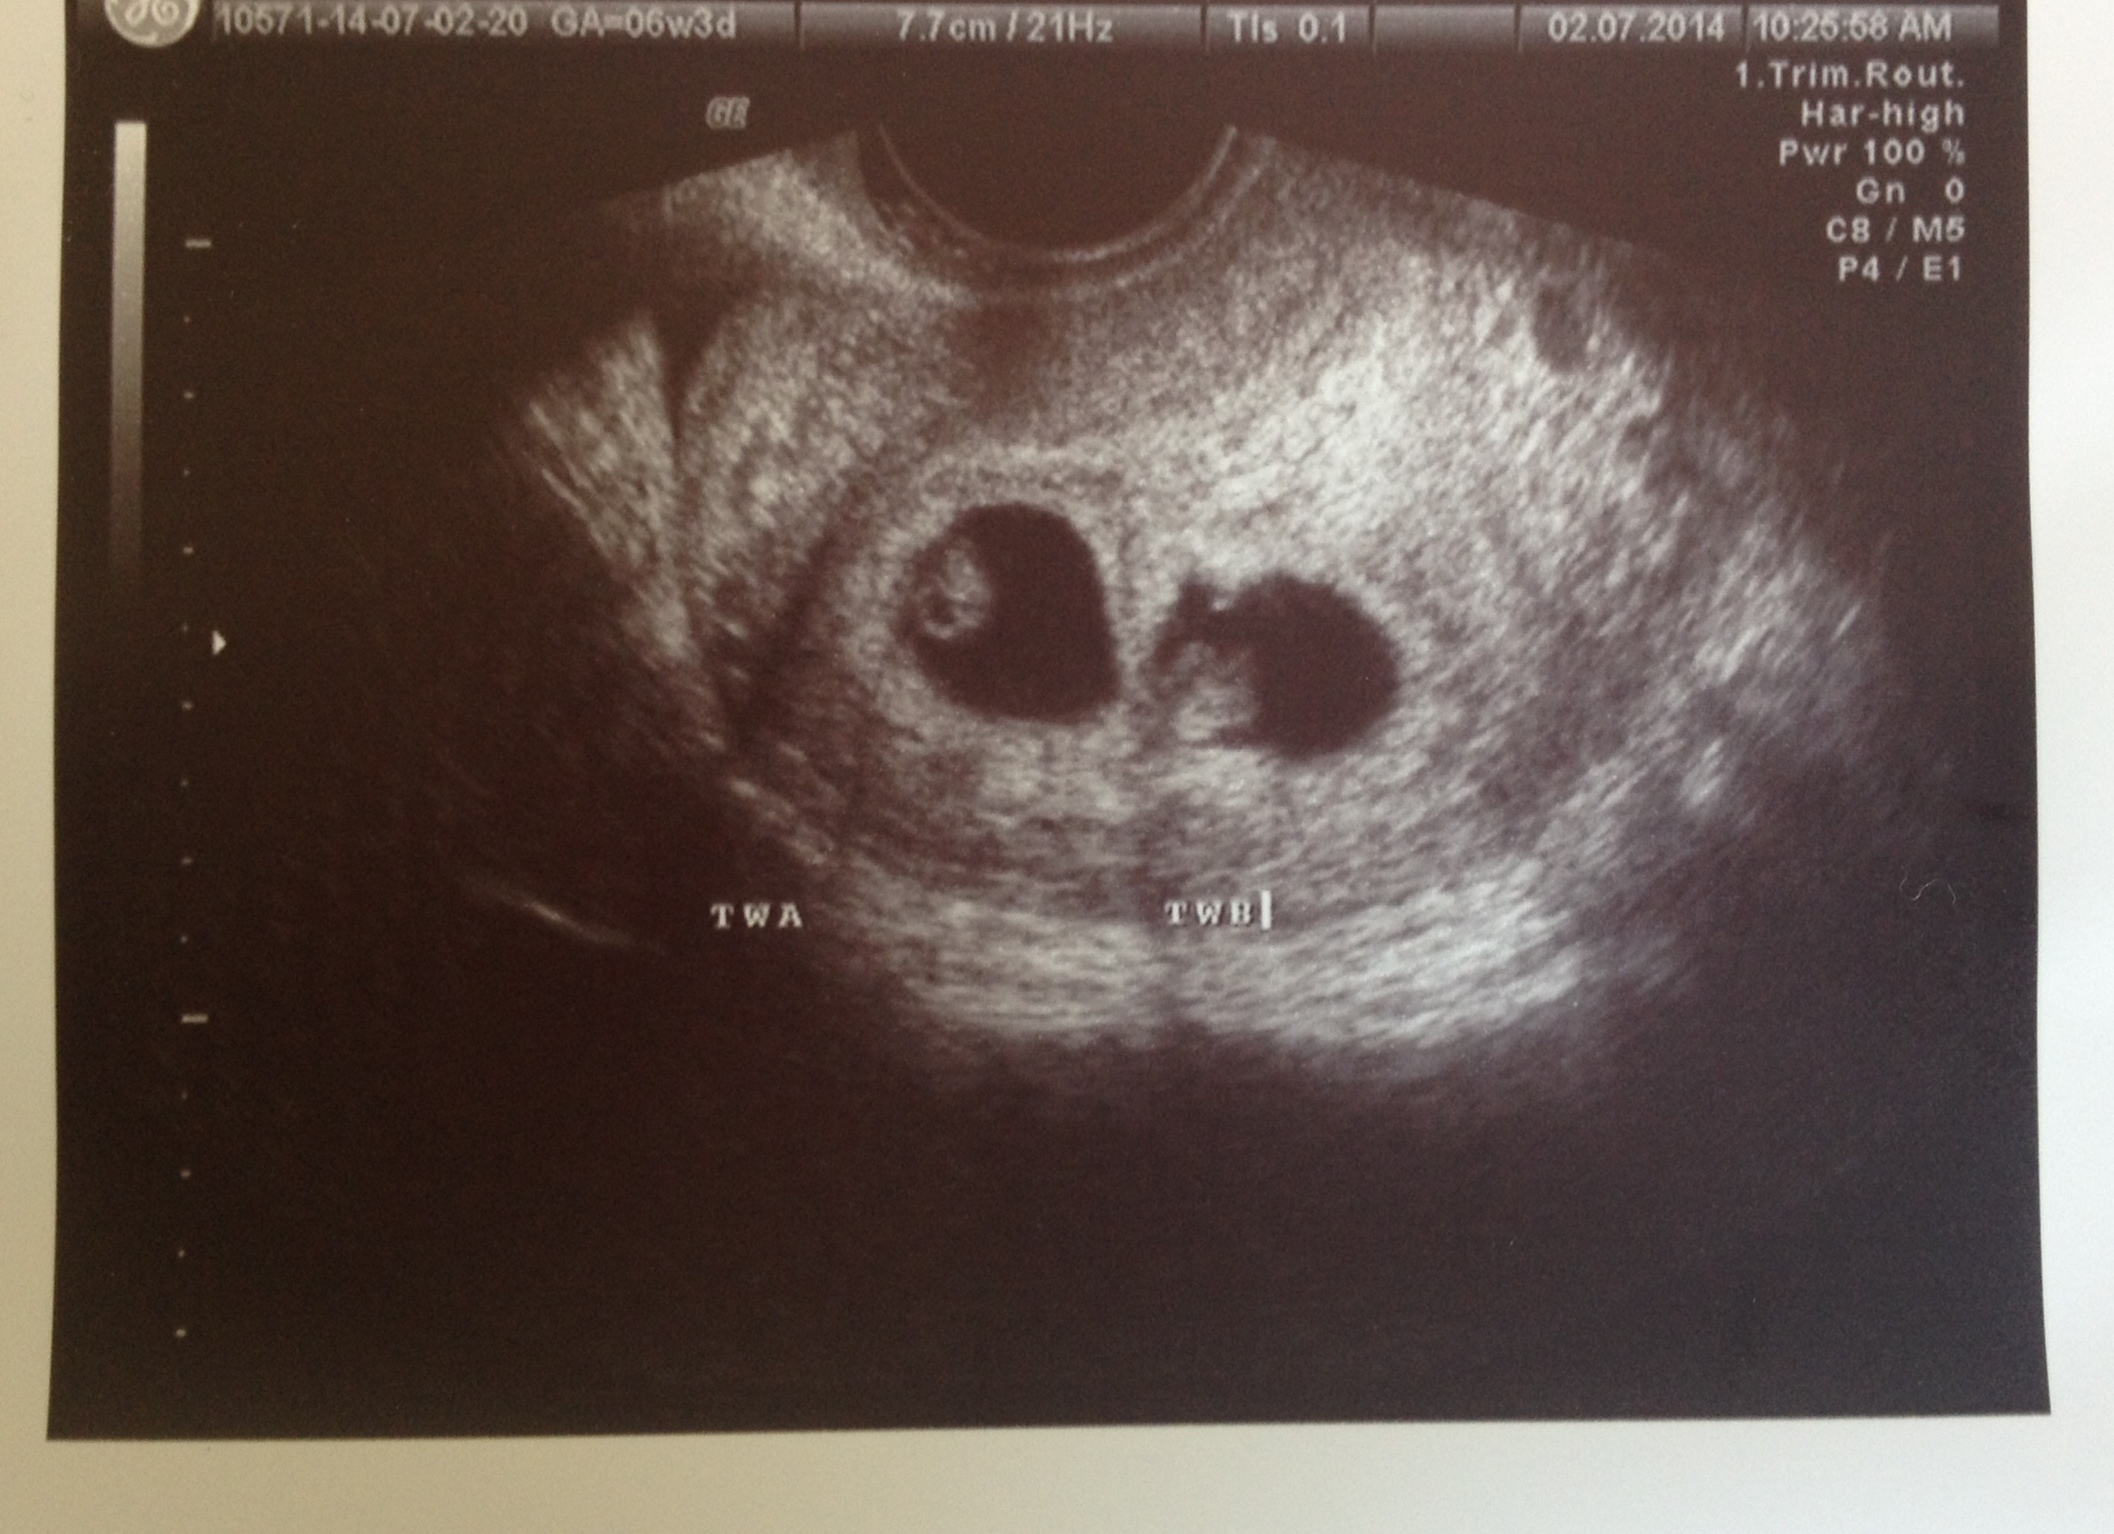

Beta #1 12dpo - 164 & progesterone - 89!, Beta #2 16 dpo - 1189, 5w3d - u/s shows TWINS!

6/19- u/s showed heartbeats! Baby A 111 & Baby B 118, both measuring 6w1d

7/3- Baby A hb 170, Baby B hb 166 - both measuring perfect.

7/18 - Baby A 165, Baby B 171 - both measuring right on track & moving all around!